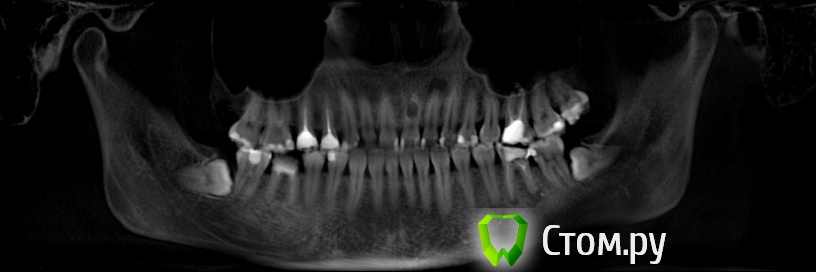

Yana5 Опубликовано 25 января, 2014 Поделиться Опубликовано 25 января, 2014 Здравствуйте, уважаемые стоматологи. В процессе лечения зубов сделала КТ, на которой случайно увидели резорбцию корня 21 зуба. Зуб вообще не беспокоит. 1)Скажите, пожалуйста, по вашему мнению, есть ли шанс вылечить этот зуб? 2) На какие еще зубы, кроме тех, где были уже пломбированы каналы обратить внимание? (нижние 6-ки уже в процессе перепломбировки каналов, 22-тоже уже пройден,8-ки в очереди на удаление ) Ссылка на комментарий

Yana5 Опубликовано 23 марта, 2014 Автор Поделиться Опубликовано 23 марта, 2014 Спасибо! Скажите пожалуйста, а почему вообще могла образоваться такая большая резорбция в здоровом зубе, это произошло практически за полтора года (на прошлом панорамном снимке за 2012 год ее не видно)? Возможно кто-нибудь из стоматологов сталкивался с таким случаем в своей практике? И еще на панорамном снимке (он в начале темы) видно затемнение вокруг корня зуба 24, что бы это могло быть, по Вашему мнению? Ссылка на комментарий

Art 7 Опубликовано 28 января, 2014 Поделиться Опубликовано 28 января, 2014 Согласен с Иваном, резорбция очень большая и в кости остаётся очень маленький фрагмент корня чтобы не произошёл перелом Ссылка на комментарий